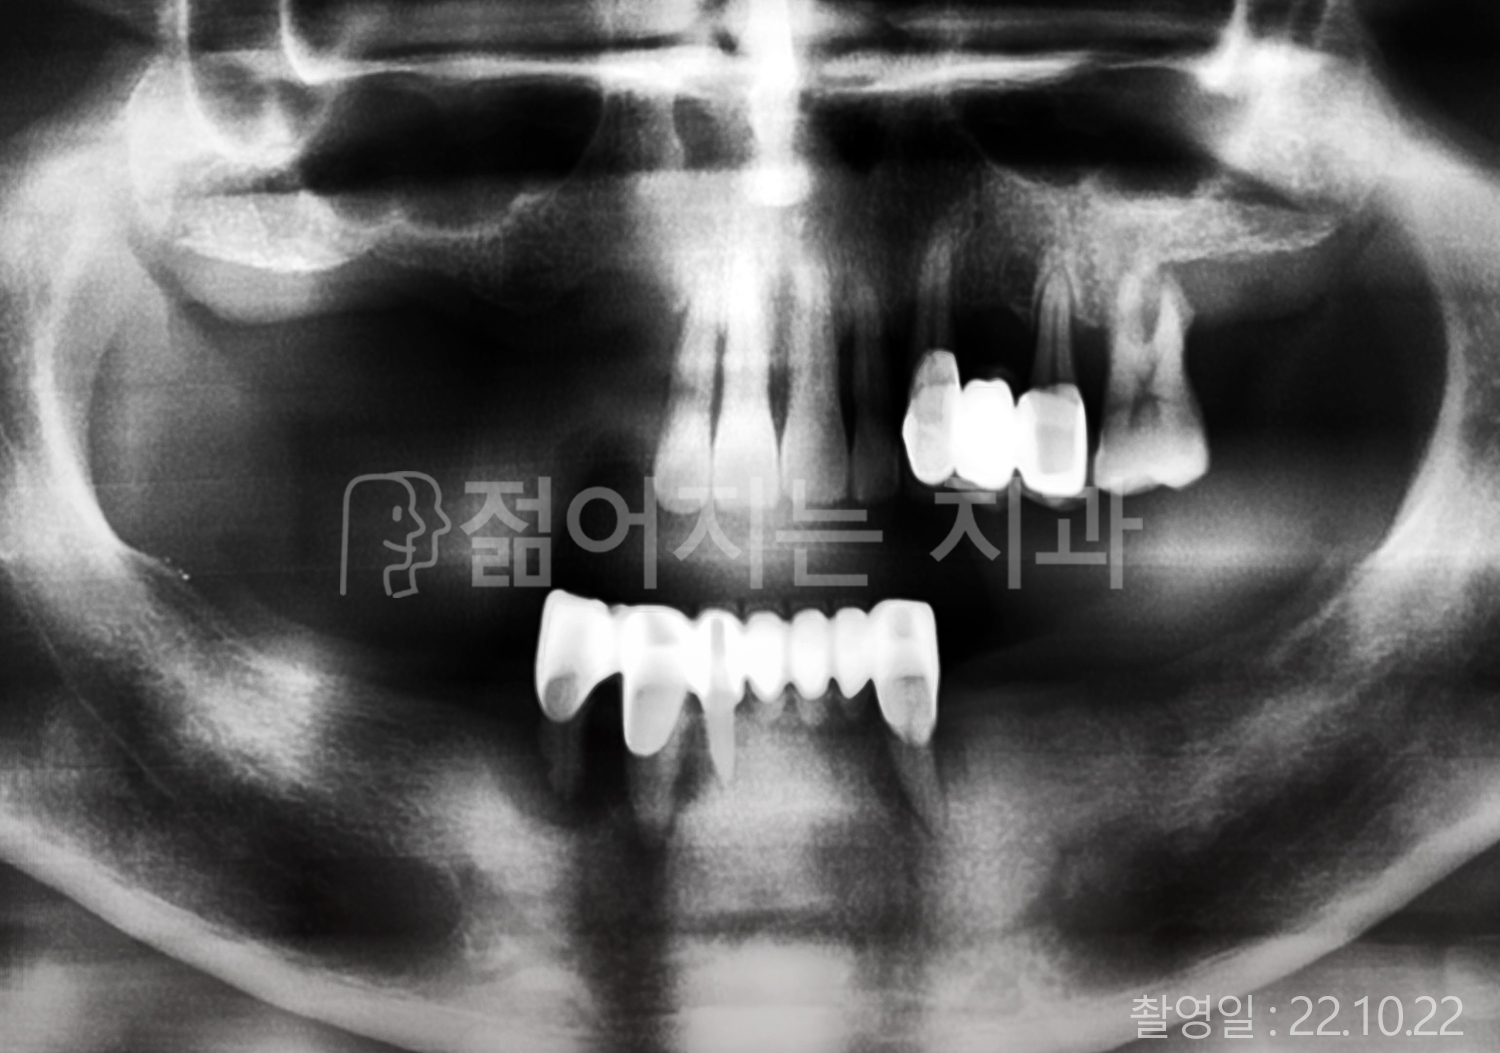

• 50대 전체치아 10개 이상 임플란트